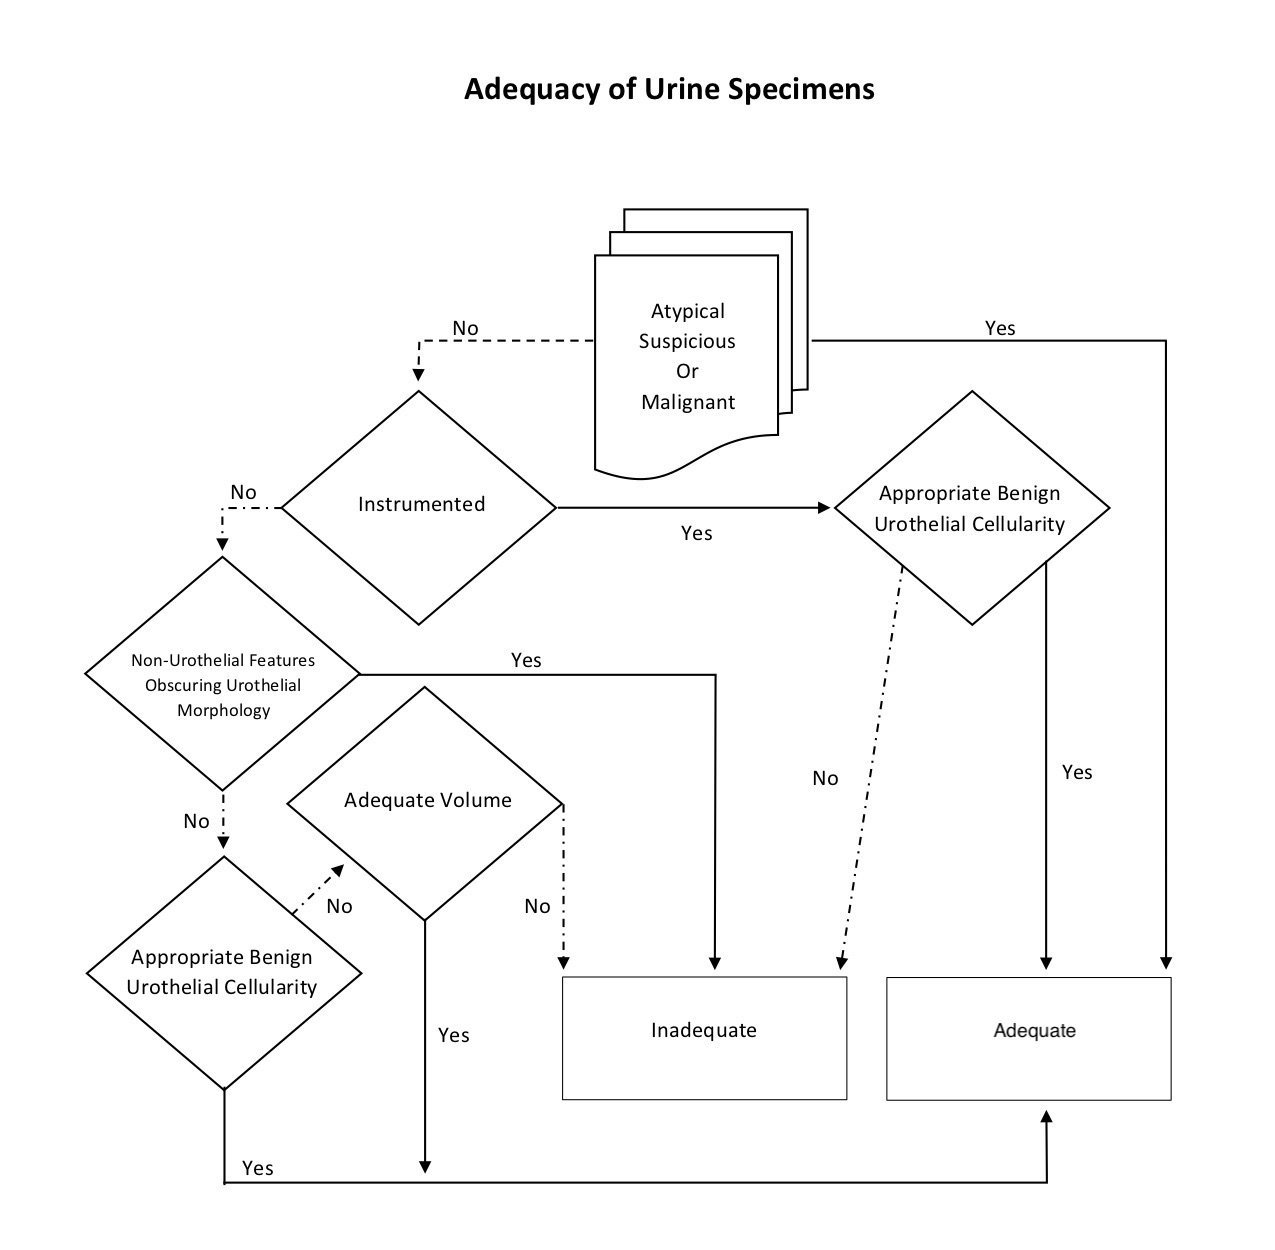

Specimen adequacy

- Adequacy refers to the usefulness of the specimen to diagnose or raise suspicion of urothelial carcinoma

- Adequacy is determined by the interplay of 4 specimen characteristics: collection type, cellularity, volume and cytomorphologic findings

- Of these, the cytomorphologic findings must be considered first because any atypical, suspicious or malignant cells make the specimen intrinsically adequate regardless of the volume, cellularity or collection type

- Similar to Pap smear adequacy, any atypical, suspicious or malignant cells on cytology automatically becomes an adequate specimen

- Adequate number of benign urothelial cells also supercedes any volume requirements for adequacy

- Volume is only considered for voided specimens; low volume samples are less likely to have adequate urothelial cells, but an optimal volume has not been established

- The Paris system indicates that for SurePath®, 30 ml is an optimal volume for voided urines but specimens should not be rejected based on low volume

- Benign urothelial cellularity cut offs should be validated for instrumented and voided urines